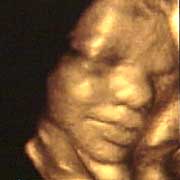

圖文:胎兒子宮內(nèi)表情豐富 專家稱提供研究新依據(jù)

中新網(wǎng)9月13日電 英國天空新聞報(bào)道,英國科學(xué)家圖亞特·坎貝爾最近利用先進(jìn)的掃描技術(shù)清晰地拍下了孕婦子宮中胎兒的表情,透過他拍攝的照片,人們可以清楚的看到一個(gè)尚未降臨世間的小生命喜、怒、哀、樂的表情。

斯圖亞特.坎貝爾是倫敦著名的產(chǎn)科教授,他利用超聲掃描技術(shù)拍攝到了胎兒在子宮中打呵欠、眨眼、吮手指、哭泣甚至微笑的畫面,這些都為胎兒行為的研究提供了新的依據(jù),專家認(rèn)為,這一突破將推動(dòng)?jì)雰航】悼茖W(xué)的發(fā)展,包括對(duì)唐氏綜合癥等嬰幼兒疾病的診治將起到極大的推動(dòng)作用。

此前,醫(yī)學(xué)界一直認(rèn)為,嬰兒要到降生后才可以做出喜、怒、哀、樂的表情,要通過模仿母親才可以學(xué)會(huì)微笑。

坎貝爾教授說:“有個(gè)這種技術(shù),現(xiàn)在許多問題都可以進(jìn)行研究了。比如說,患有唐氏綜合癥的嬰兒和正常嬰兒的活動(dòng)方式是否一樣?胎兒是否因?yàn)楦吲d才笑?胎兒哭是否是因?yàn)樵谧訉m中受到打擾?既然我們都認(rèn)為子宮內(nèi)是一片黑暗,那胎兒為什么會(huì)眨眼呢?”(章田)